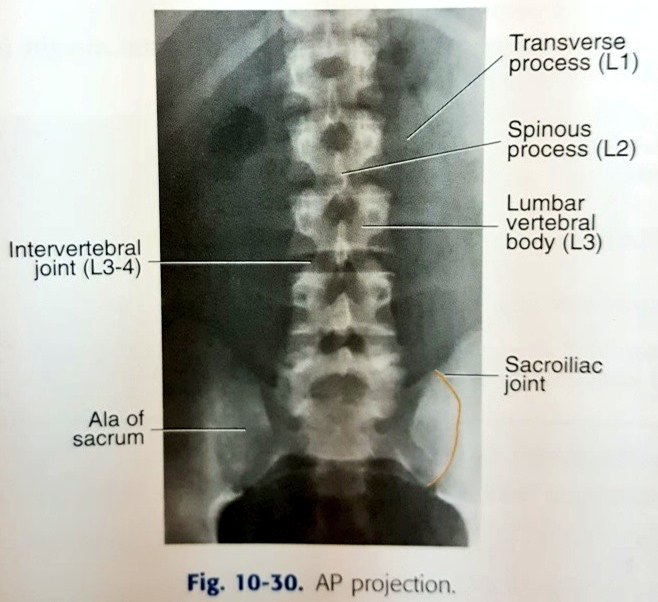

☆٥الفحص الأمامي للفقرات القطنية

AP view of Lumbar spine

معلومات/

•الفقرات القطنية عددها ٥ فقرات.

•أهم فقرة هي القطنية رقم ٣ ،لأنه يتم استخدامها كمركز للشعاع.

•يتم الاستدلال على موقعها بأنها تقع على مستوى حافة الأضلاع السفلى.

Lower costal margin

الوضع:

المريض مستلقي على ظهره.

¤وضع prone أفضل للنساء لأنه يوفر حمايةإشعاعيةللمبايض بنسبة 25%-30%¤

•نتأكد أن الحوض غير ملتف أو مائل عن طريق ضبطه بالطلب من المريض أن يسترخي ثم نقوم بالإمساك بمنطقة أعلى الوركين ونرفعه عن الطاولة ثم إفلاته.

•ثني الركبتين وملامسة القدمين للطاولة.

الفائدة من ثني الركبتين وجعل القدمين تلامس الطاولة تقليل (الإنحناء) في الفقرات القطنية

(lordosis)

و حتى يصبح الدسك بين الفقرات موازي للشعاع.

التنفس/

يقوم بإخراج الهواء وايقاف التنفس.

السنتر CR/

L3

●تقييم الفلم/

نعرف عدم وجود إلتفاف

أنspinous process

في منتصف الفقرات✔